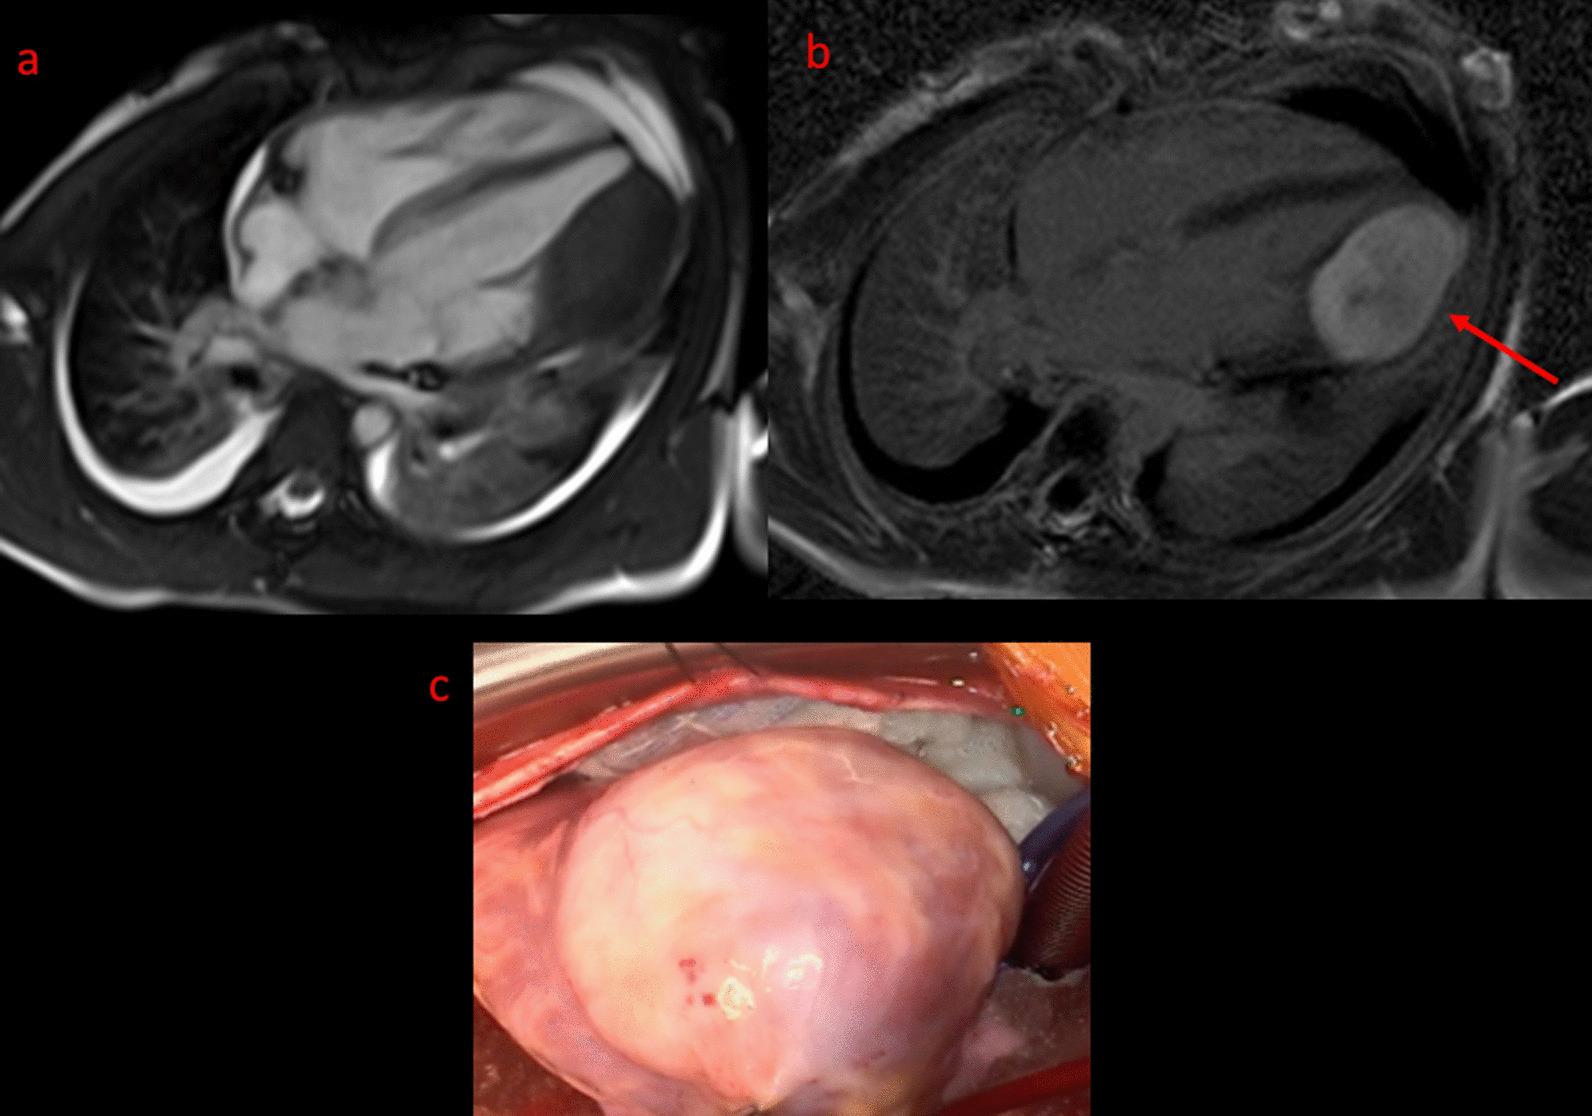

Cardiovascular magnetic resonance (CMR) has been utilized in the management and care of pediatric patients for nearly 40 years. It has evolved to become an invaluable tool in the assessment of the littlest of hearts for diagnosis, pre-interventional management and follow-up care. Although mentioned in a number of consensus and guidelines documents, an up-to-date, large, stand-alone guidance work for the use of CMR in pediatric congenital 36 and acquired 35 heart disease endorsed by numerous Societies involved in the care of these children is lacking. This guidelines document outlines the use of CMR in this patient population for a significant number of heart lesions in this age group and although admittedly, is not an exhaustive treatment, it does deal with an expansive list of many common clinical issues encountered in daily practice.

心血管磁共振(CMR)在儿科患者的管理和护理中已经应用了近 40 年。它已经发展成为评估最小的心脏的宝贵工具,用于诊断、介入前管理和随访。尽管在许多共识和指南文件中提到,但在儿科先天性心脏病和后天性心脏病领域,目前还缺乏一份由众多参与儿童护理的学会共同认可的、最新的、独立的、针对 CMR 使用的大型指南。本指南文件概述了 CMR 在该年龄段的许多心脏病变中的应用,尽管不能说是详尽的治疗方法,但它确实涉及了在日常实践中经常遇到的许多常见临床问题的广泛列表。